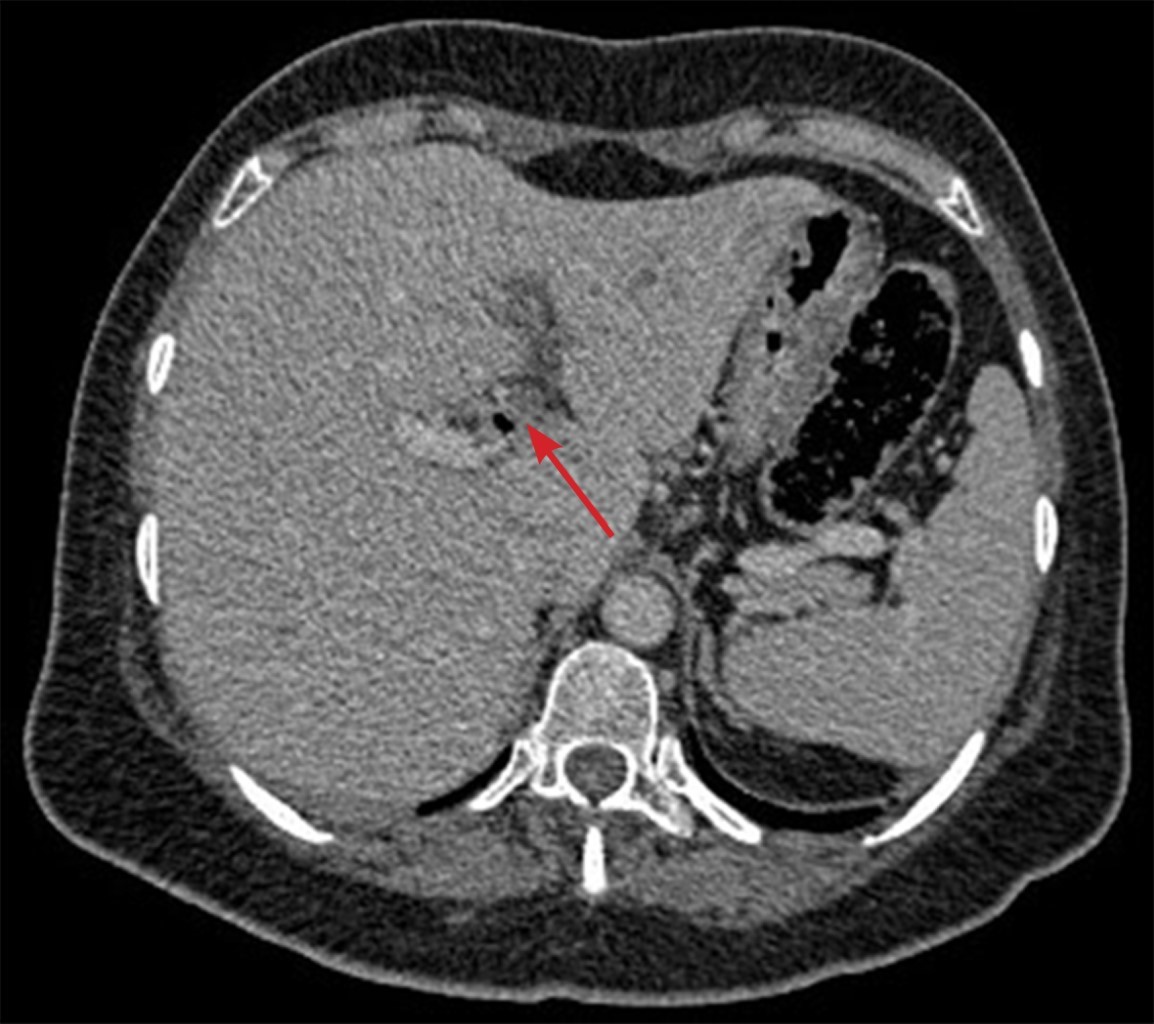

Introduction: pylephlebitis, also known as ascending septic thrombophlebitis, is characterized by embolic occlusion of the portal-venous system and its branches, secondary to intra-abdominal infection. Clinical case: a 63-year-old female came for abdominal pain, as well as a fever of 39.4 °C. They presented leukocytosis, increased C-reactive protein, procalcitonin, and liver function tests. A tomography was performed, observing air thrombus in the inferior mesenteric vein and thrombus in the left portal vein, with data of diverticulitis. Conclusions: pylephlebitis is a rare and severe complication; the radiologist must identify it to establish the appropriate medical treatment.

Figure 2